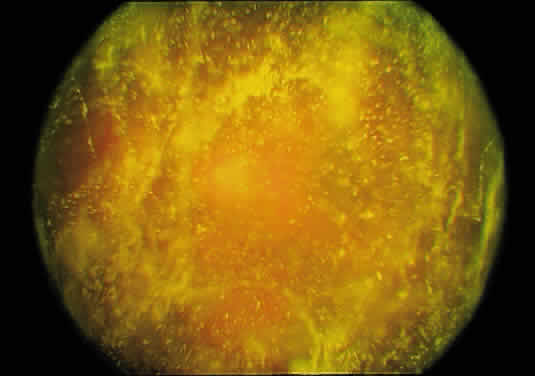

Although vitreous is the largest structure within the eye, comprising 80% of its volume, our knowledge of vitreous structure and function is perhaps the least of all ocular tissues. Historically, investigations of vitreous structure have been hampered by two fundamental difficulties: first, any attempts to define vitreous morphology are attempts to visualize a tissue that is invisible by design (Fig. 1).1 Considerable barriers must be overcome to adequately study the structure of an invisible tissue. Second, the various techniques that were used previously to define vitreous structure were fraught with artifacts that biased the results of these investigations. Thus, as noted by Baurmann2 and Redslob,3 histologic studies performed during the nineteenth and early twentieth centuries were flawed by the use of tissue fixatives that caused the precipitation of what we recognize today as the glycosaminoglycan (GAG) hyaluronan (HA; formerly called hyaluronic acid).

Fig. 1. Vitreous from a 9-month-old child. The sclera, choroid, and retina were dissected off the vitreous, which remains attached to the anterior segment. Because of the young age of the donor, the vitreous is almost entirely gel. Thus, the structure is solid and maintains its shape, although situated on a surgical towel exposed to room air. A band of gray tissue can be seen posterior to the ora serrata. This is peripheral retina that was firmly adherent to the vitreous base and could not be dissected away without disrupting the vitreous base. (Courtesy of the New England Eye Bank, Boston, MA)